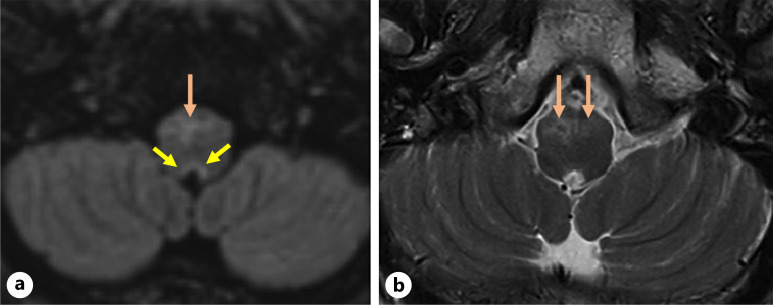

Case presentation: A previously healthy man in his 70s presented with headache, fever, and confusion, followed by a seizure and persistent hiccoughs. MRI revealed brainstem involvement and extensive transverse myelitis. Cerebrospinal fluid (CSF) analysis showed inflammatory features, but testing for AQP4, MOG, and GFAP antibodies was initially negative. He was treated with intravenous corticosteroids and plasma exchange, after which serum GFAP-IgG was weakly positive, though CSF remained negative. His condition improved with immunotherapy, but significant lower limb weakness persisted. Based on clinical and radiological findings, we hypothesize that tanycytes - specialized glial cells in the area postrema - may be an additional immune target in GFAP encephalitis.

Conclusion: This case highlights a seronegative encephalomyelitis syndrome with area postrema involvement, possibly implicating glial cells beyond astrocytes. Further studies are needed to explore the role of tanycytes in autoimmune neuroinflammation.